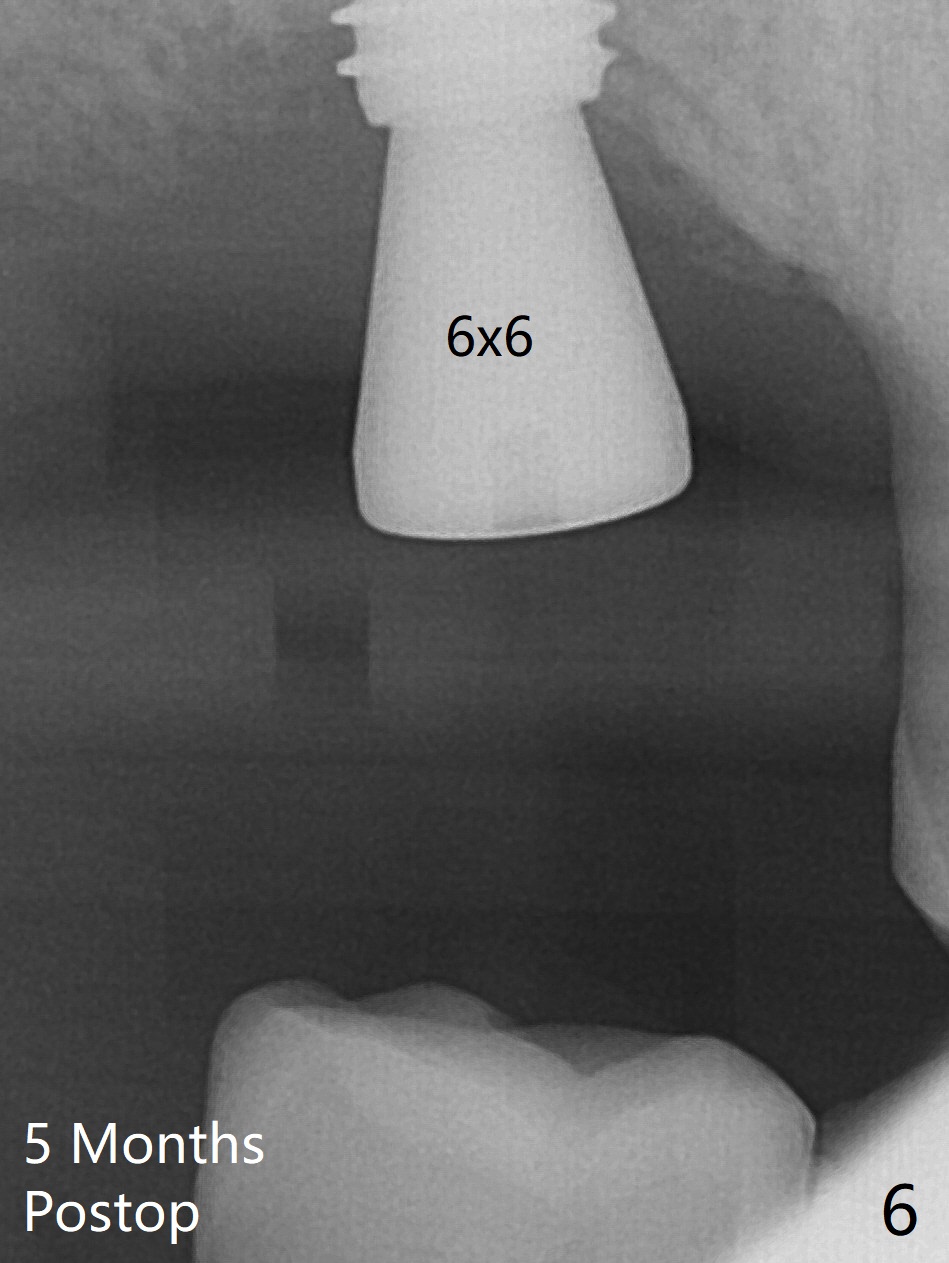

Two things happen immediately before this surgery. A SM implant is found to fail related to bruxism and poor oral hygiene, ~ 5 years in function; a UF implant will be used instead. DIO Sinus Approach Kit has not been autoclaved; therefore the free-hand one has to be used with caution. In fact the procedure goes on apparently smoothly in spite of the fact that the patient with medical knowledge is nervous about the risk of sinus lift. After 4.0x8.5 mm Neo Navi drill with 12 mm offset, the 3.6 mm sinus safety drill is used from 7 to 9 mm in length, followed by water balloon, PRF membranes (x2) and mixture of autogenous bone graft and allograft and 4.5x10 mm dummy implant (Fig.1). The definitive implant is placed with satisfactory stability (Fig.2), but a 6.5x7(4) mm healing abutment is close to the mesial crest (*). The former is reloaded following 6.0 mm Bone Profile Drill (Fig.3) and then is changed to a 6x6 mm IS one. The patient reports nasal hemorrhage immediately returning home, but there is no similar episode a few hours later. Re-analysis of preop (Fig.4) and immediate postop (Fig.5) CT shows that water balloon technique in fact swells the sinus membrane (M) instead elevating it. It is safe to place more bone graft (Fig.5 *). There is pain when the 6x6 mm healing abutment is being removed nearly 5 months postop (Fig.6.7). The patient complains of mild sinus discomfort, although panoramic X-ray does not show abnormality (Fig.8). He will return for recheck for implant stability (low bone density) before impression 2-4 months later.